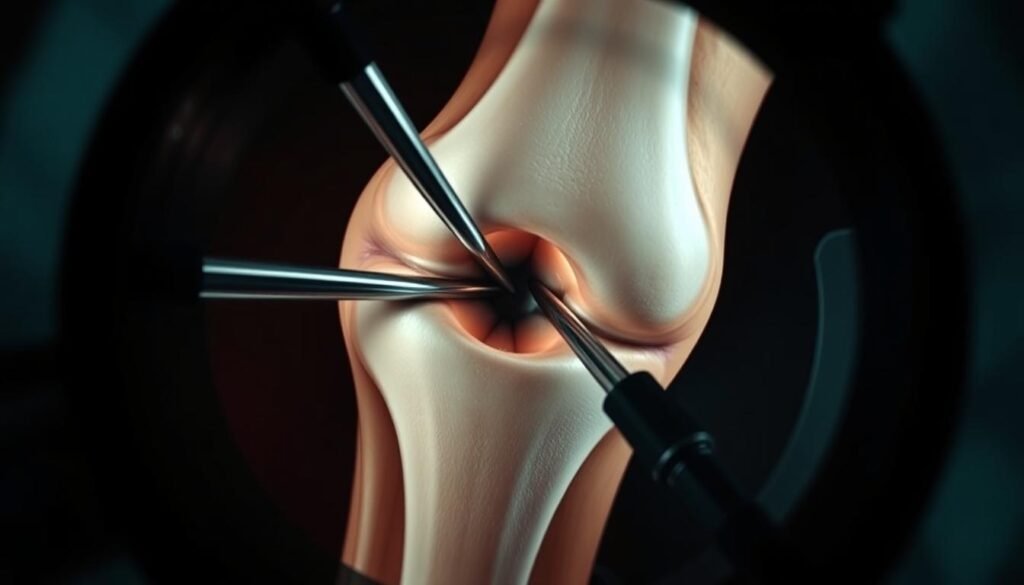

Minimalinvasive Verfahren bei Arthrose

Wenn konservative Maßnahmen nicht ausreichend helfen, bieten minimalinvasive Verfahren eine schonende Alternative zur offenen Operation.

Arthroskopische Eingriffe ermöglichen präzise Behandlungen mit minimalen Schnitten

Arthroskopie (Gelenkspiegelung)

Die Arthroskopie ermöglicht durch kleine Schnitte einen direkten Blick ins Gelenkinnere und gleichzeitig therapeutische Eingriffe:

- Entfernung freier Gelenkkörper

- Glättung aufgerauter Knorpeloberflächen

- Behandlung von Meniskusrissen

- Entfernung entzündeter Gelenkschleimhaut